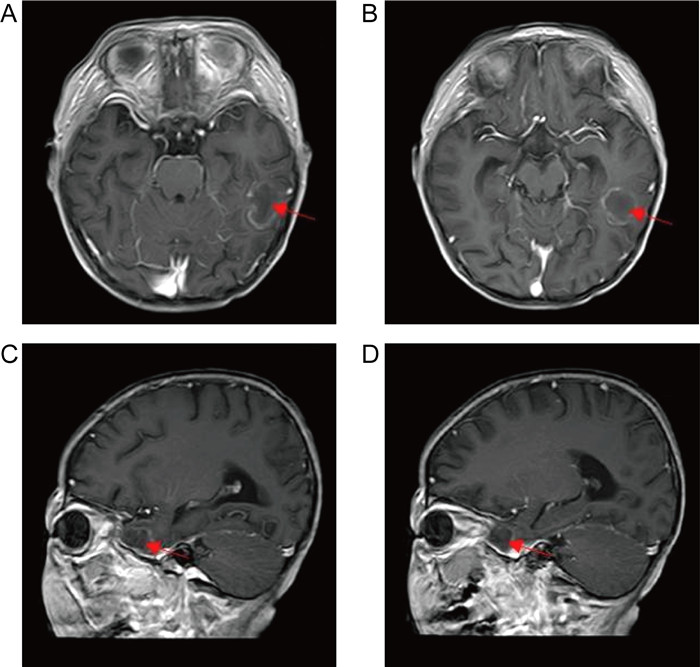

1.3 病情变化及预后患儿入院即存在中性粒细胞缺乏伴发热,感染控制后予以诱导缓解治疗(VDLD):长春新碱(vincristine)+柔红霉素(daunorubicin)+培门冬(pegaspargase)+地塞米松(dexamethasone)。患儿第13天再次出现发热,多次调整抗感染方案,先后曾给予美洛培南、万古霉素、伏立康唑、卡泊芬净、两性霉素B等抗感染治疗,体温控制欠佳,无热期1~2天,C反应蛋白(C-reactive protein,CRP)最高升至216 mg/L,降钙素原为2.27 ng/mL。期间多次完善胸部计算机断层扫描(computed tomography,CT)、腹部超声,均未提示明确异常。血培养、骨髓培养、脑脊液培养提示无菌生长,1,3-β-D葡聚糖抗原检测及半乳甘露聚糖抗原检测试验(G/GM试验)结果为阴性。VDLD诱导缓解治疗第19天患儿诉上门齿疼痛,经口腔科会诊及颌面部超声检查未提示明显异常,VDLD治疗第30天患儿出现左侧眼睑肿胀,伴有少量分泌物,给予妥布霉素滴眼液滴眼。VDLD诱导缓解治疗完成后第2天,患儿出现右侧鼻出血,左侧鼻腔流涕,且伴有喉中痰鸣,完善痰培养,并于耳鼻喉科行鼻腔镜检查,镜下双侧鼻腔可见血痂、干酪样物质,右侧中鼻甲、鼻中隔黏膜糜烂、吸收、缺如,骨质裸露、部分缺损,中鼻道霉菌团块,后鼻孔见坏死性干痂(见图 1),鼻腔分泌物行涂片检查: 找到真菌无隔菌丝(见图 2),分泌物及痰培养提示霉菌生长(见图 3)。急查头颅CT,见左侧颞叶低密度。行头颅磁共振成像(magnetic resonance imaging,MRI)平扫+增强,提示:左侧颞叶多发异常信号,右侧基底节区及左侧颞叶多发弥散受限灶,右侧颞叶病变内强化灶;蝶窦、左侧鼻腔、左侧上额窦、筛窦信号增高,结构欠清,前额部部分软脑膜明显强化,结合患者的病史,考虑真菌感染可能性大(见图 4)。患儿发热期间曾给予两性霉素B静滴,终因肾功能损害及低钾血症而暂停应用。患儿鼻眶脑型毛霉菌病诊断明确后立即给予两性霉素B脂质体(锋克松)静点,初始剂量0.5 mg/kg/d,逐渐增至2.5 mg/kg/d维持,同时予泊沙康唑90 mg/次,一日4次口服;期间给予两性霉素B雾化及鞘内注射,鞘内注射初始剂量为0.1 mg,逐渐增加至最大1 mg,每周2~3次,出院前共鞘注7次,两性霉素B总量为3.55 mg,期间因患儿头痛、血压高而减少鞘注剂量。患儿在接受两性霉素B脂质体抗真菌治疗期间出现肾功能损害及低血钾,予以调整两性霉素B脂质体剂量及静脉补钾治疗。应用两性霉素B脂质体抗真菌治疗后患儿热峰降低,C反应蛋白降至15 mg/L,左侧眼睑肿胀减轻,精神状态较之前明显好转,但患儿出现左侧上睑下垂,左眼球活动障碍,双侧瞳孔不等大,视物不清,复查头颅磁共振增强扫描,提示:脑内多发异常信号,右侧基底节区病变略缩小,余病变较前增大(见图 5), 建议家属待患儿血象恢复后手术切除感染灶,家属要求出院,院外继续口服泊沙康唑,未行手术及化疗,半年后死于白血病复发。

| 图 1 鼻腔镜检查 Fig. 1 Nasal endoscopy examination |